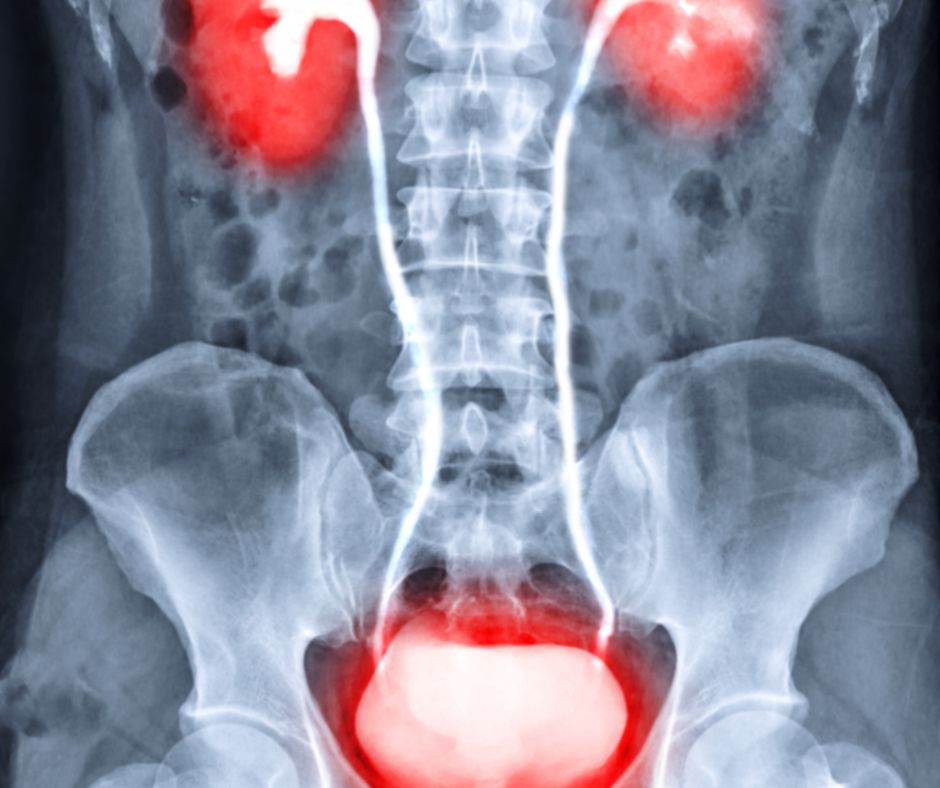

Močové cesty tvoria dôležitý systém v tele, ktorý zabezpečuje tvorbu, zhromažďovanie a vylučovanie moču z organizmu. Tento systém sa skladá z nasledujúcich štyroch hlavných častí:

- Obličky: Obličky sú párové orgány nachádzajúce sa v zadnej časti brucha. Každá osoba má dve obličky, umiestnené na oboch stranách chrbtice. Hlavnou úlohou obličiek je filtrovanie krvi a odstraňovanie odpadových látok a nadbytočnej tekutiny. Taktiež regulujú rovnováhu elektrolytov a krvného tlaku.

- Močovody: Močovody sú úzke trubice, ktoré vychádzajú z obličiek a vedú moč do močového mechúra. Každá oblička je spojená s jedným močovodom. Močovody transportujú moč pomocou peristaltických sťahov svalových stien.

- Močový mechúr: Močový mechúr je dutý svalový orgán, ktorý slúži na zhromažďovanie moču. Nachádza sa v panve a môže sa rozšíriť až do určitej kapacity, keď sa naplní močom. Močový mechúr je schopný udržať moč až do doby, kým sa nevyvolá nutkanie na močenie.

- Močová rúra (uretra): Močová rúra je trubica, ktorá vedie moč z močového mechúra von z tela. U žien je kratšia a vedie von z tela priamo nad otvorom pošvy. U mužov je dlhšia a prechádza cez penis. Močová rúra u mužov plní aj funkciu prenosu spermií počas ejakulácie.